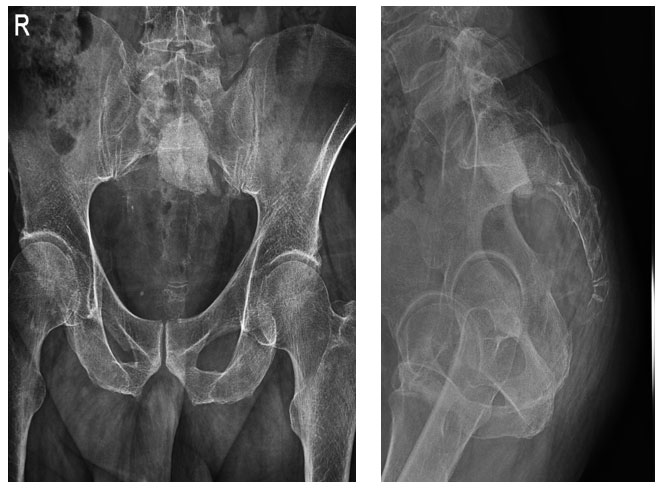

Ameliyat Esnası: Her iki birinci sakral kökün korunması, rekonstrüksiyon işlemi ve lokal flep ile yaranın kapatılması görülmekte.